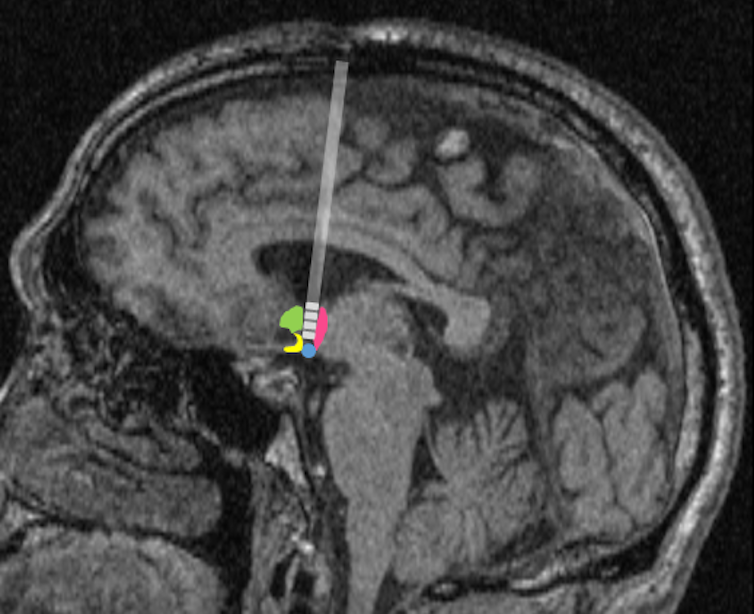

Deep brain stimulation is an FDA-approved treatment for many neurological disorders such as Parkinson’s disease. It consists of implanting, through the skull, stimulating electrodes, with electric wires, into deep structures inside the brain. These electrodes are then connected to pacemaker-like devices in the patient’s chest. The pacemaker devices produce an electric signal that modifies the brain activity and improves the targeted symptoms, such as tremor in Parkinson’s disease.

In Alzheimer’s disease, the memory circuits in the brain, which include a notable structure called the fornix, are affected. The fornix is important in remembering personal events and concepts. In the ADvance trial, the researchers evaluated if deep brain stimulation at the level of the fornix ameliorated the memory of 42 subjects with Alzheimer’s disease. They found a possible improvement in memory only in those older than 65; researchers saw no benefit when evaluating all the participants. Learning from this experience, the researchers are embarking on another trial called ADvance II.